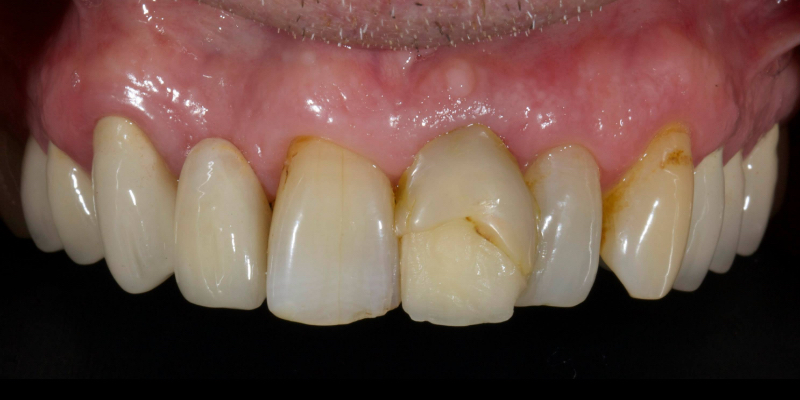

Here’s John’s case bonded with heated resin. He had a failing, older metal, ceramic adhesive bridge (Fig. 18). The bridge was carefully removed (Fig. 19) and the final bridge was seated (Fig. 20).